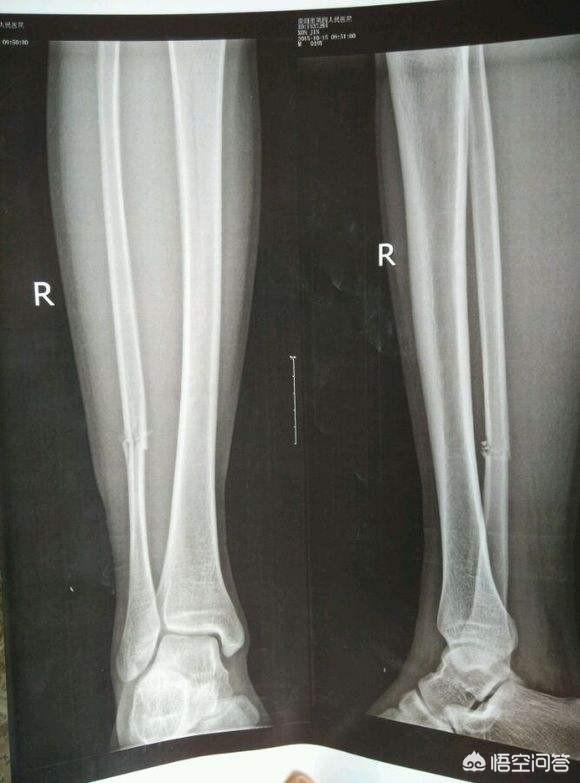

X线胫骨腓骨骨折内固定术后照片 正版商用图片164f8f 摄图新视界